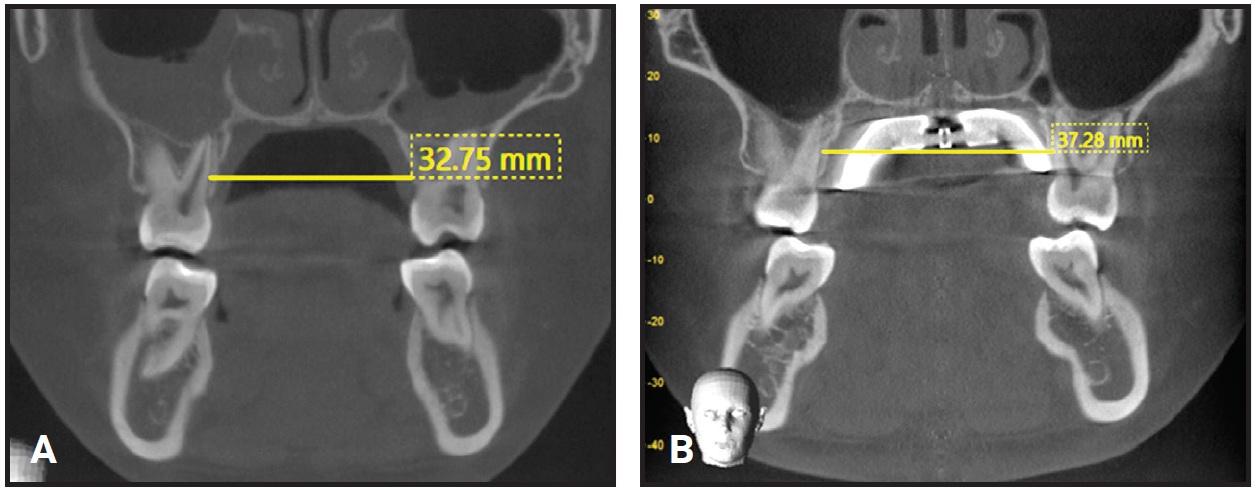

Clinical examination showed an oval face with a biprotrusive profile, a mandibular shift to the right, and competent lips. The patient had a Class I canine relationship on the right side, with the upper canine out of occlusion, and Class II molar and canine relationships on the left. A severe upper dental midline shift to the right, a constricted upper arch, and severe crowding in both arches were also observed. The upper right lateral incisor and upper left central and lateral incisors were in crossbite. A 21mm upper arch-width discrepancy was measured between the distal aspects of the second molars.

Analysis of the digital models indicated increases of 4.8mm in arch width between the upper first premolars, 2.6mm in arch width between the upper first molars, and 5mm in total arch length between the distal aspects of the second molars (Fig. 7, Table 2).

Fig. 7 Arch-width changes. A. Before expansion. B. One week after expansion. C. Superimposition of digital models before and one week after expansion.

Fig. 8 Maxillary width and angulation of first molars. A. Before treatment. B. One week after expansion.